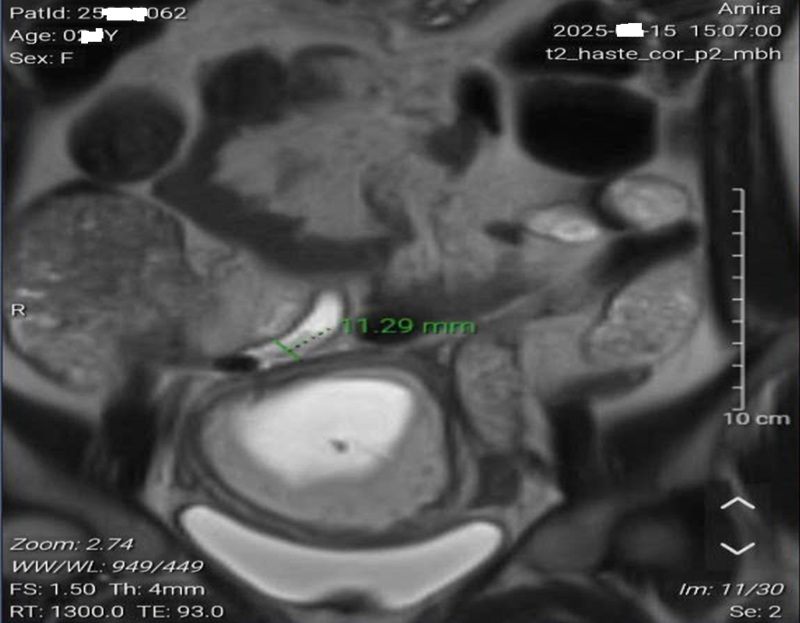

Kết quả siêu âm ổ bụng của bệnh nhân không có gì bất thường. Tuy nhiên, xét nghiệm máu cho thấy hội chứng hủy hoại tế bào gan khi chỉ số AST và ALT rất cao, lần lượt là 457 và 624 U/L.